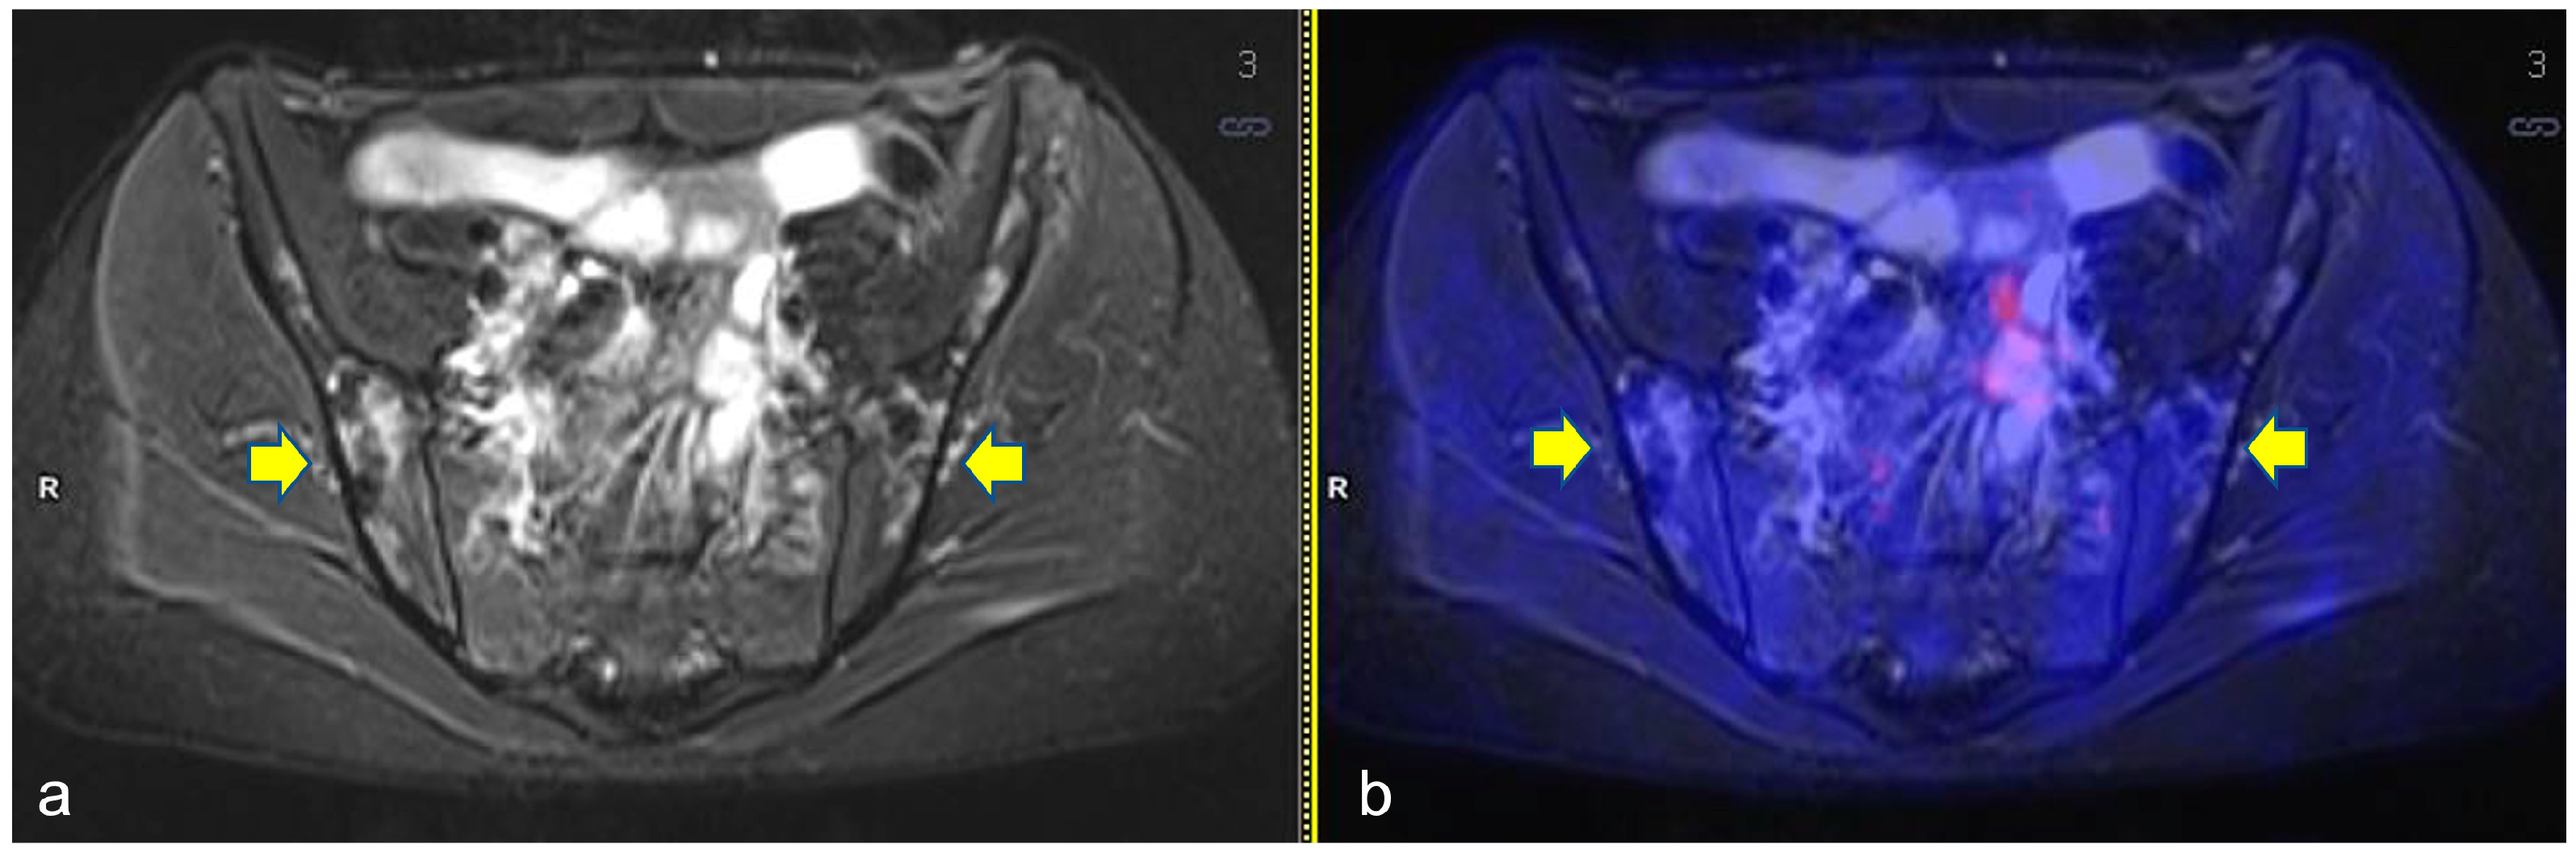

| Pts | TL | HL Disease Bone Involvement at Diagnosis | BILs Site Involvement | N. of Lesions | PET-MR Time-Point |

|---|---|---|---|---|---|

| 1 | 3 | Yes | bilateral distal femur diaphysis; right proximal tibia metaphysis and left proximal tibia diaphysis | 4 | ERA PET-MR |

| 2 | 2 | No | right iliac wing; proximal humerus epiphysis; bilateral proximal femurs epiphysis | 5 | ERA PET-MR |

| 3 | 3 | No | right iliac wing; sacrum; bilateral proximal femoral metaphysis | 4 | ERA PET-MR |

| 4 | 3 | No | left proximal humerus epiphysis; iliac wings; S2 vertebrae | 5 | Follow-up (+9 months from diagnosis) |

| 5 | 2 | No | right iliac wing | 1 | Follow-up (+7 months from diagnosis) |

| 6 | 3 | Yes | left proximal tibia epiphysis; left proximal femur diaphysis | 2 | ERA PET-MR |

| 7 | 2 | No | right proximal humerus epiphysis; bilateral proximal femur epiphysis; right scapula | 4 | Follow-up (+6 months from diagnosis) |

| 8 | 2 | No | left distal femoral diaphysis | 1 | ERA PET-MR |

| 9 | 2 | No | mid-proximal left femur diaphysis; left proximal humerus metaphysis | 2 | ERA PET-MR |

| 10 | 3 | No | bilateral proximal femur epiphysis | 2 | Follow-up (11 months from diagnosis) |